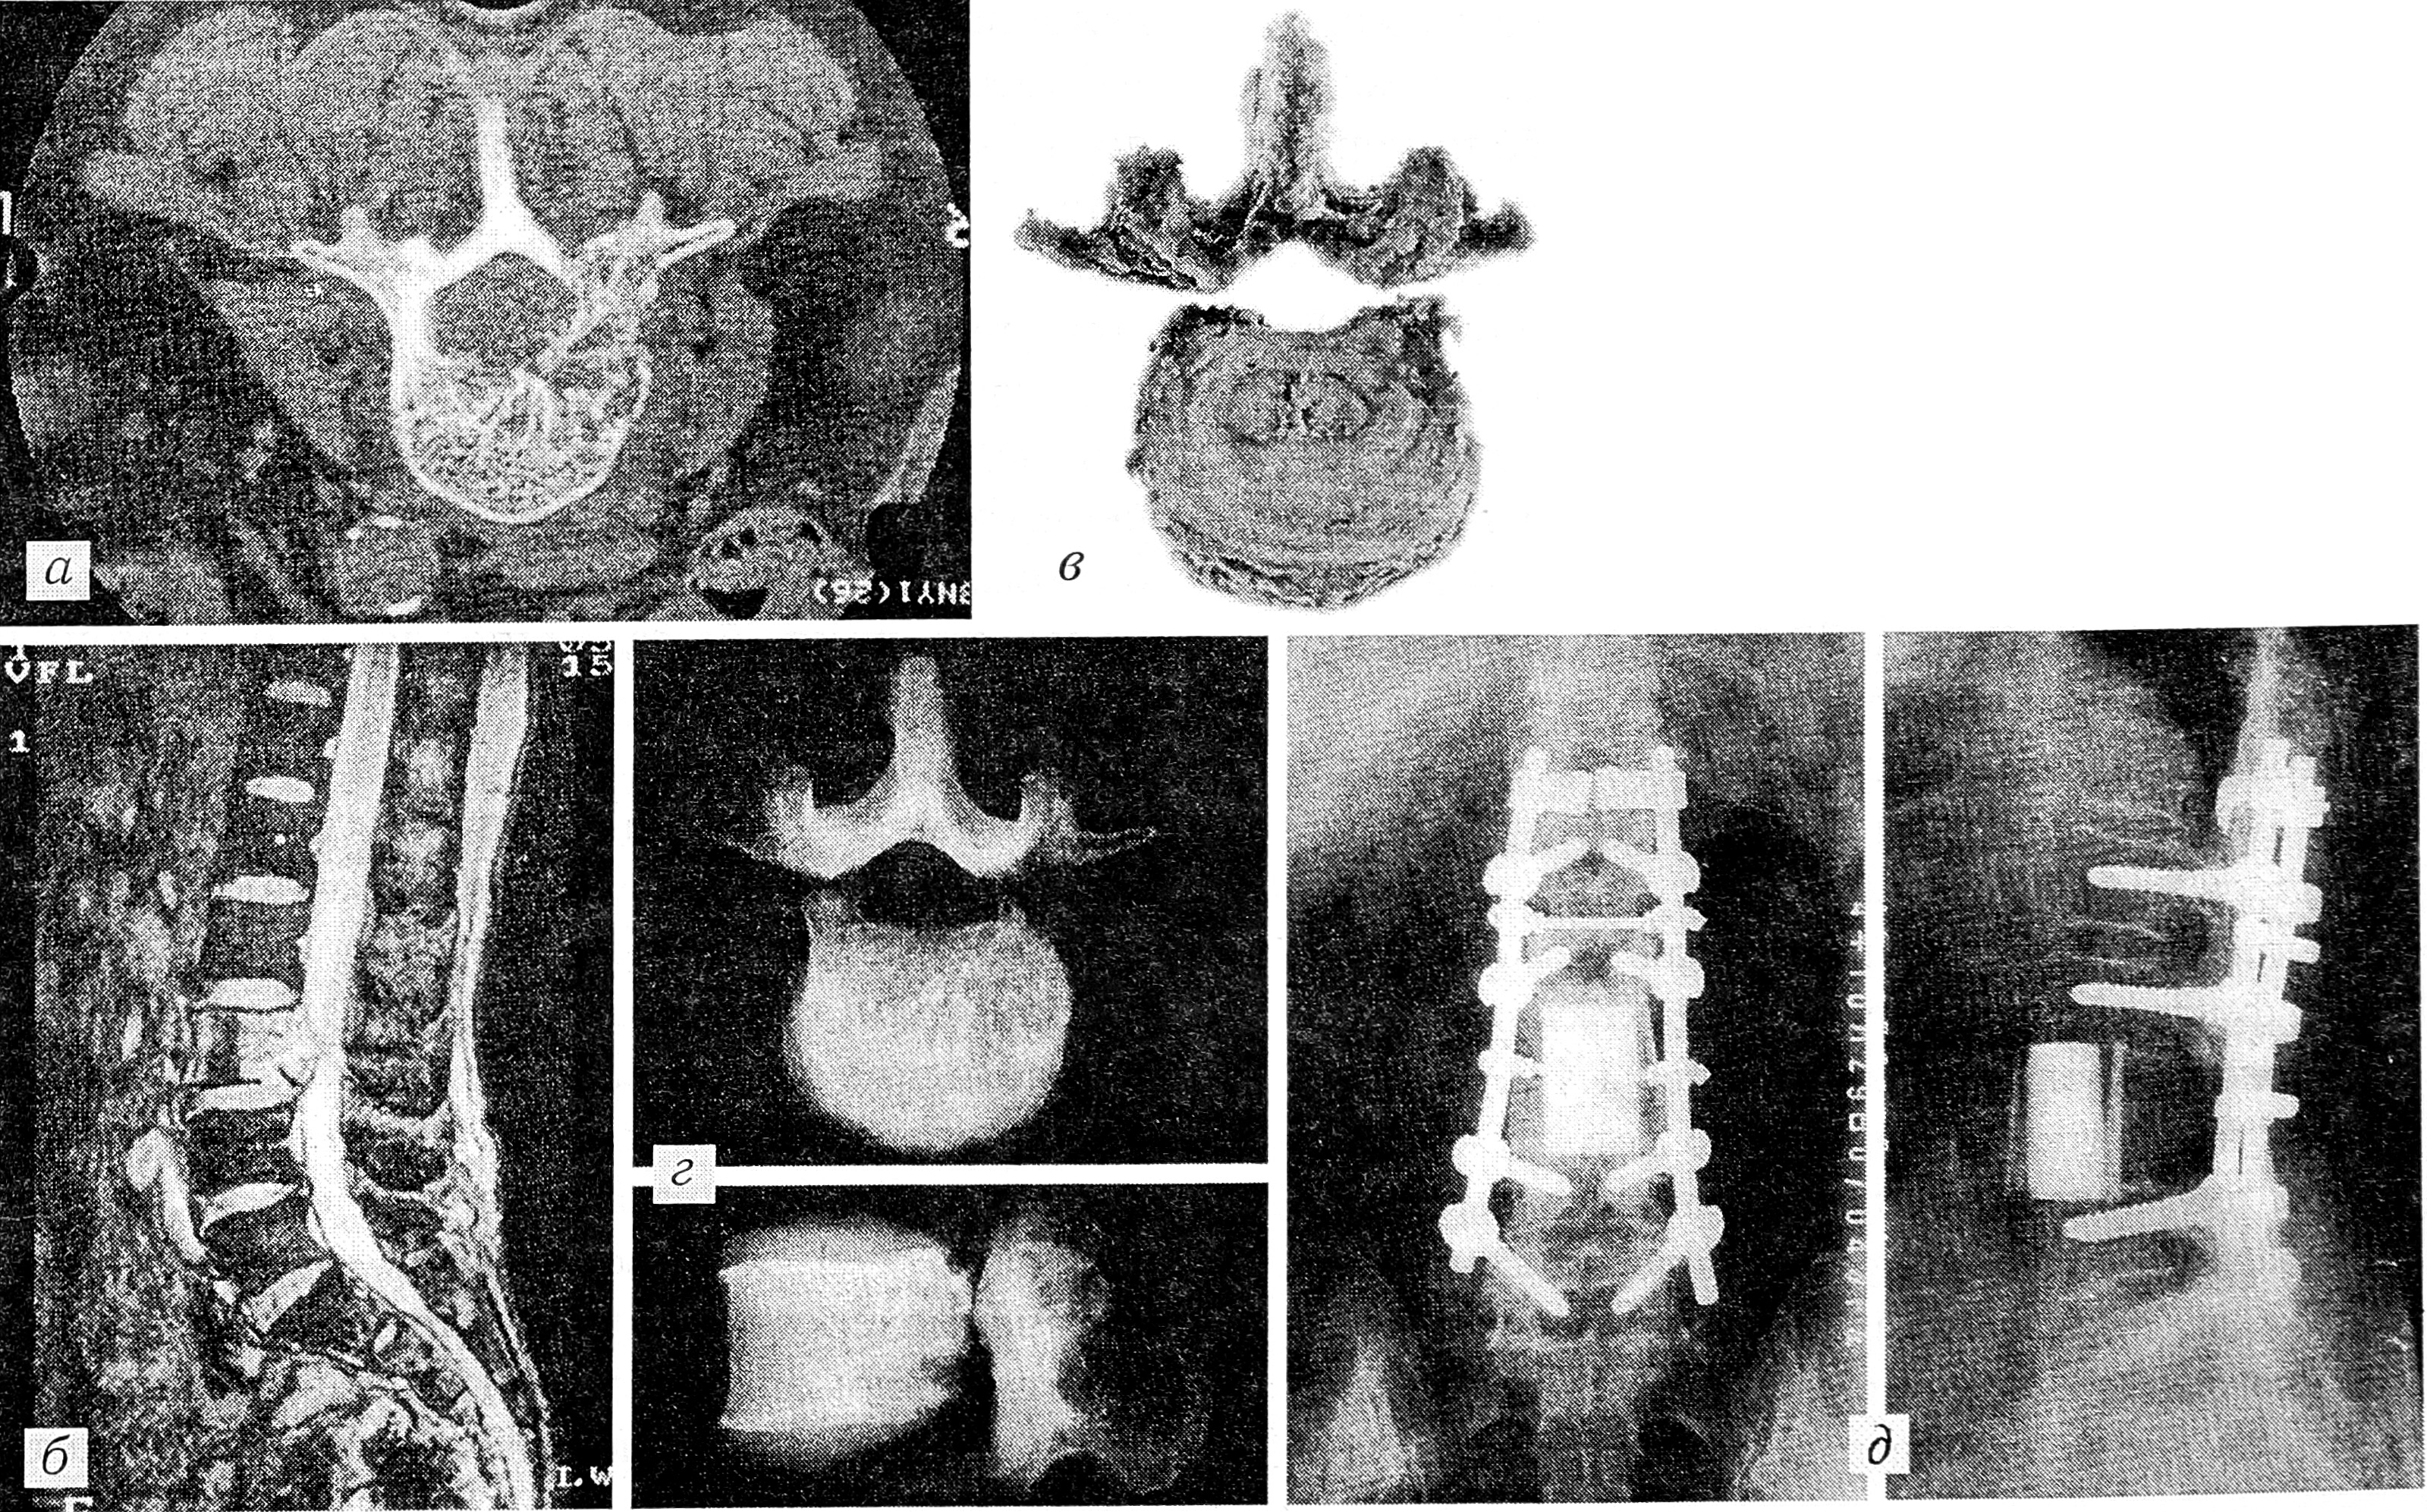

Рис. 7: а – компьютерная томограмма на уровне L3 позвонка (опухолевое поражение тела, ножки и дуги – тип 3); б – магнитно-резонансная томограмма (опухоль проникает в спинномозговой канал); в – препарат позвонка, удаленного при спондилэктомии единым блоком; г – рентгенограммы резецированного L3 позвонка; д – рентгенограммы пораженного участка позвоночника после реконструкции его с помощью устройств CD и импланта из апатит-волластонита, усиленного аллотрансплантатами.